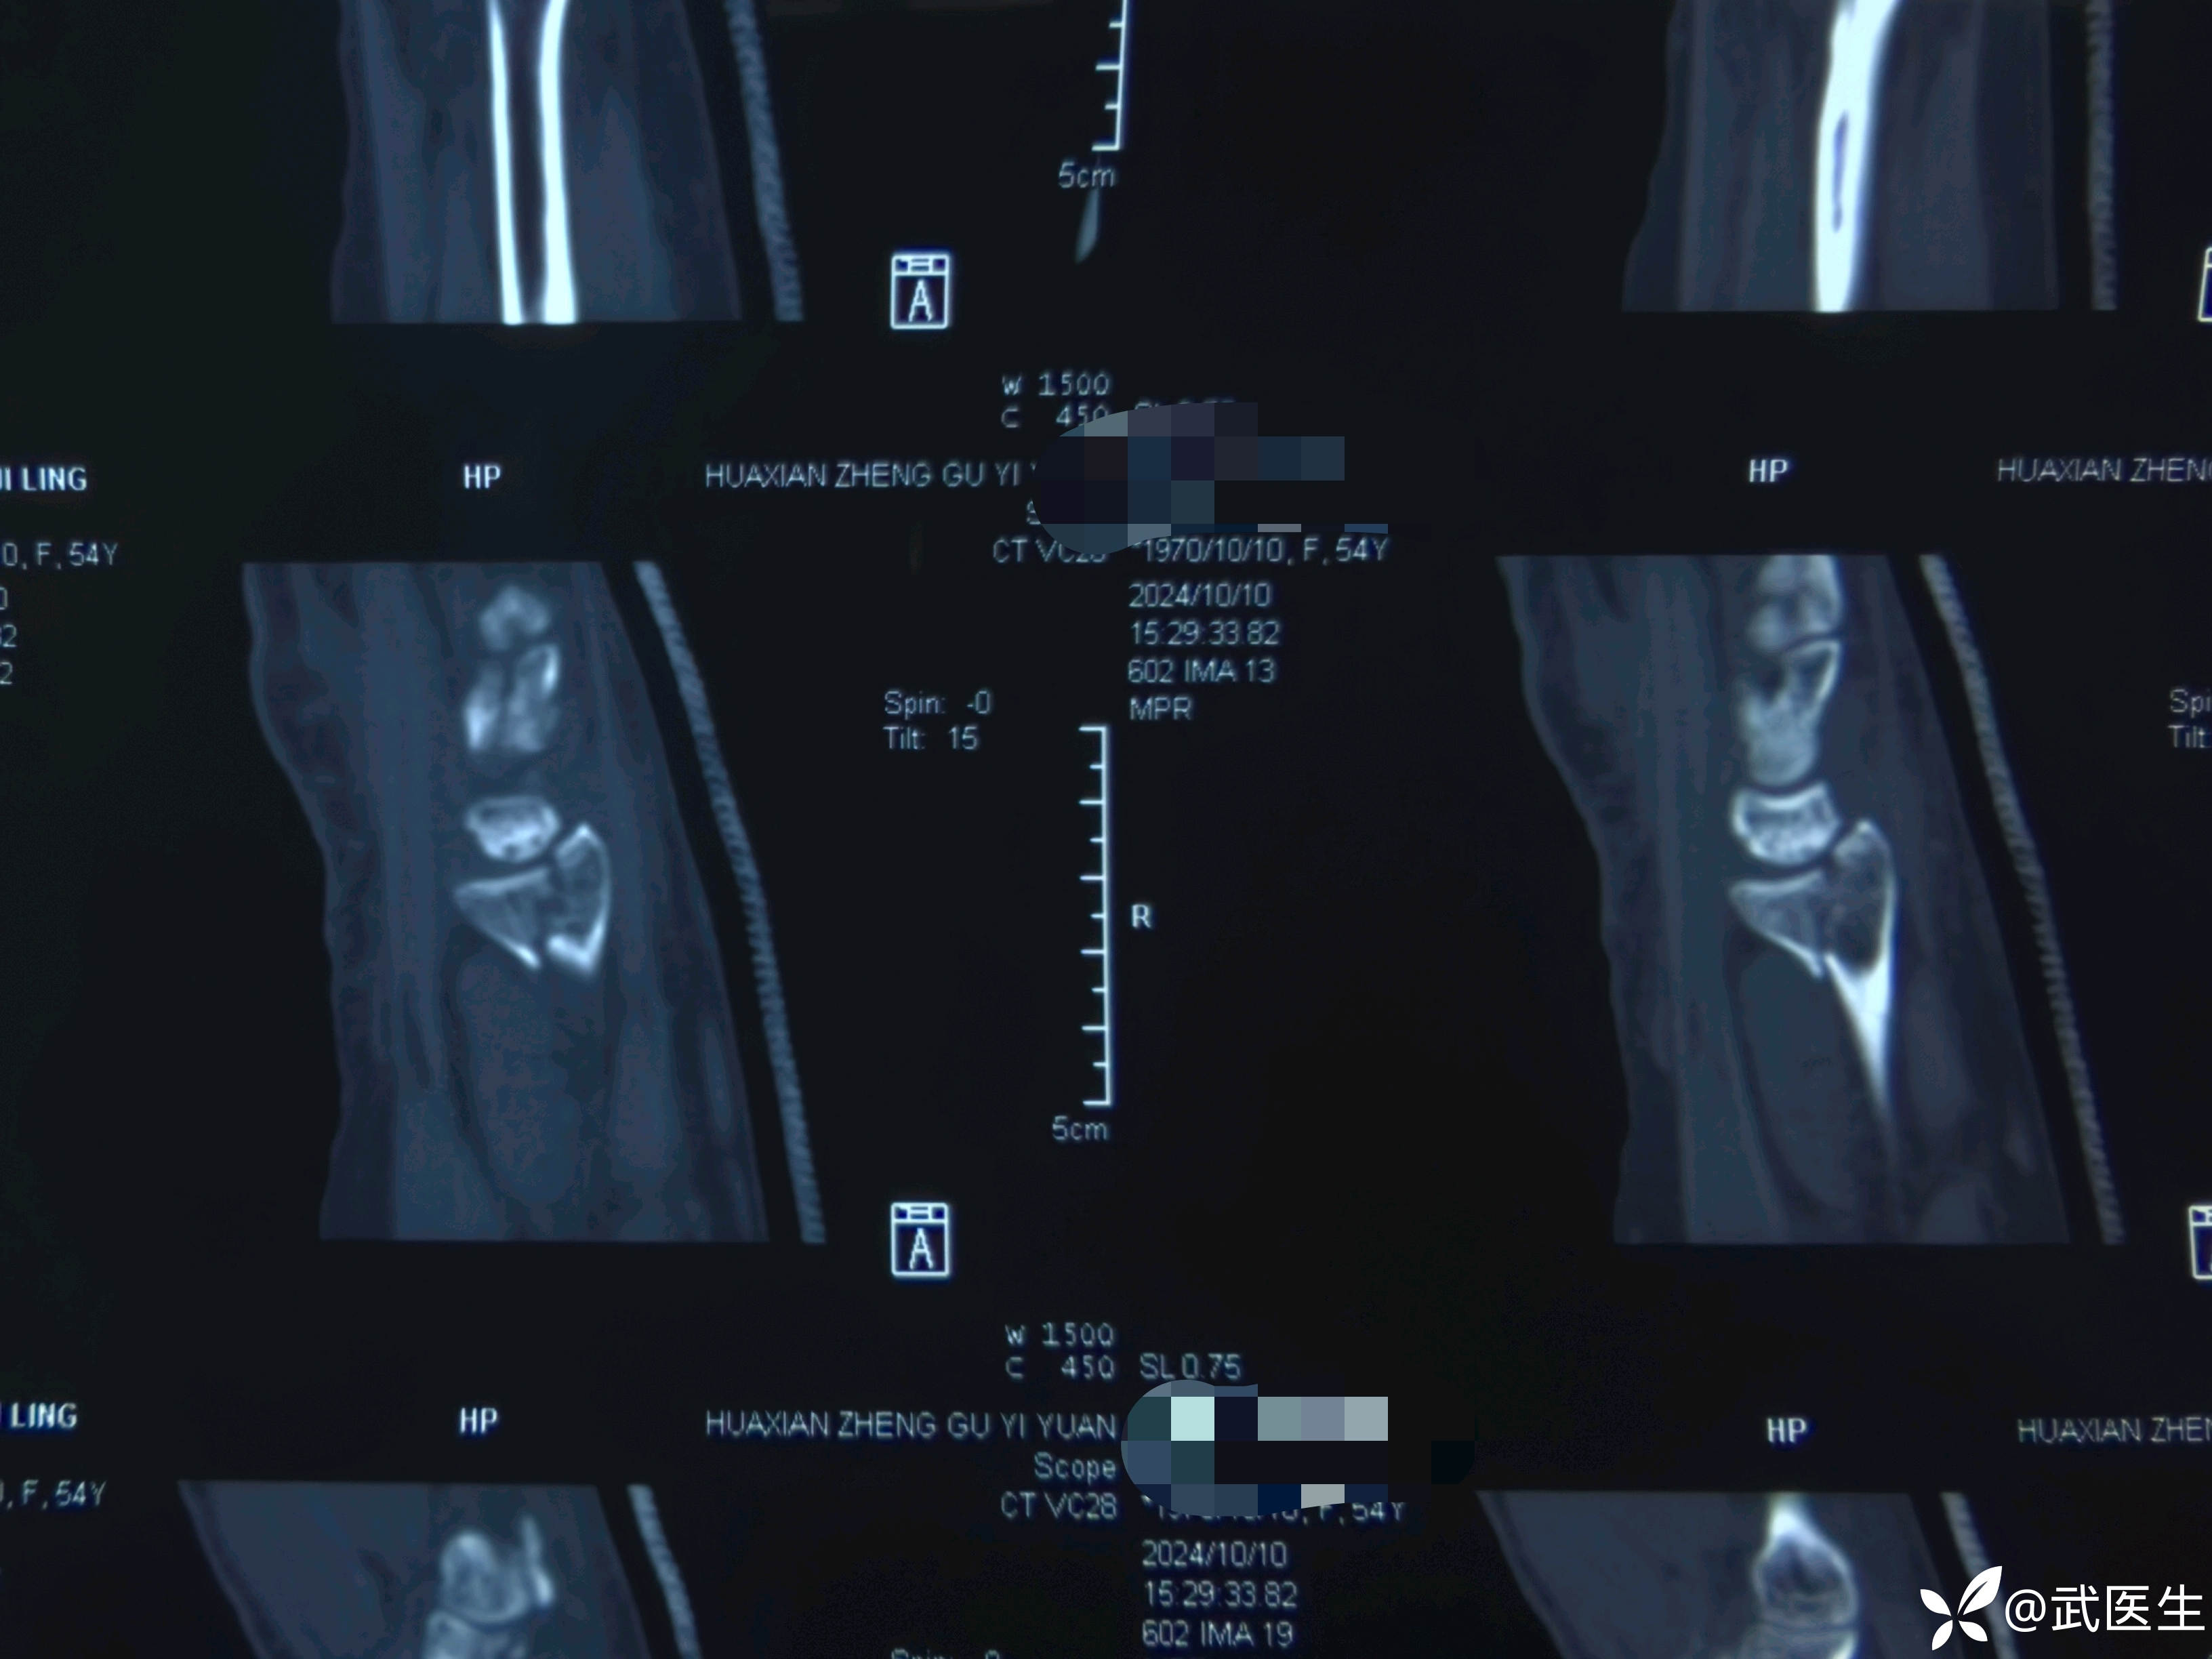

影像学检查如下

腕关节片子系外院带来

【临床诊断】:右肱骨外科颈四部分骨折脱位,左桡骨远端骨折伴桡腕关节半脱位。钩骨骨折。头面部软组织损伤。